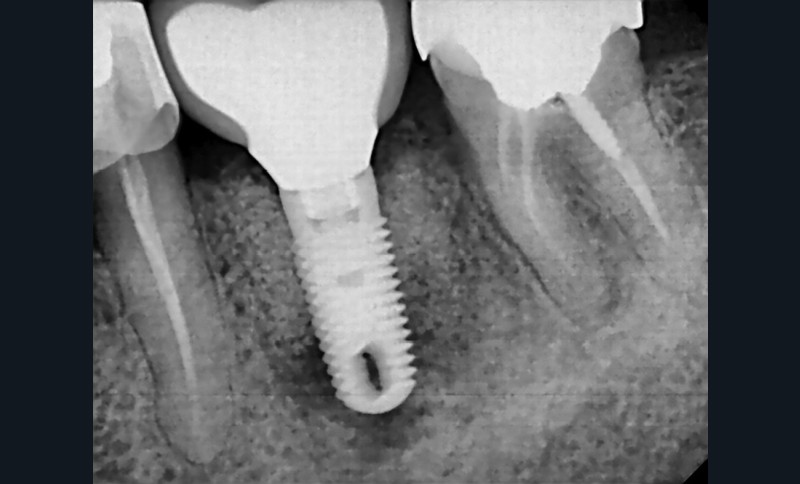

La préservation de l’ostéointégration dépend de la santé des tissus péri-implantaires mais aussi du contrôle des forces occlusales (fig. 1) [2].

D’après la récente classification de Chicago (2017) des maladies parodontales et péri-implantaires, la péri-implantite est définie comme une pathologie induite par un biofilm dysbiotique, et caractérisée par une inflammation de la muqueuse péri-implantaire et par une perte progressive du support osseux. C’est donc un processus inflammatoire le plus souvent lent et irréversible qui atteint les tissus mous et durs péri-implantaires [3]. L’étude menée par Mombelli et coll. en 2012 montre que 20 % des patients chez qui il a été posé des implants et 10 % des implants posés déclareront une péri-implantite dans les cinq à dix ans après la pose (fig. 2) [4].